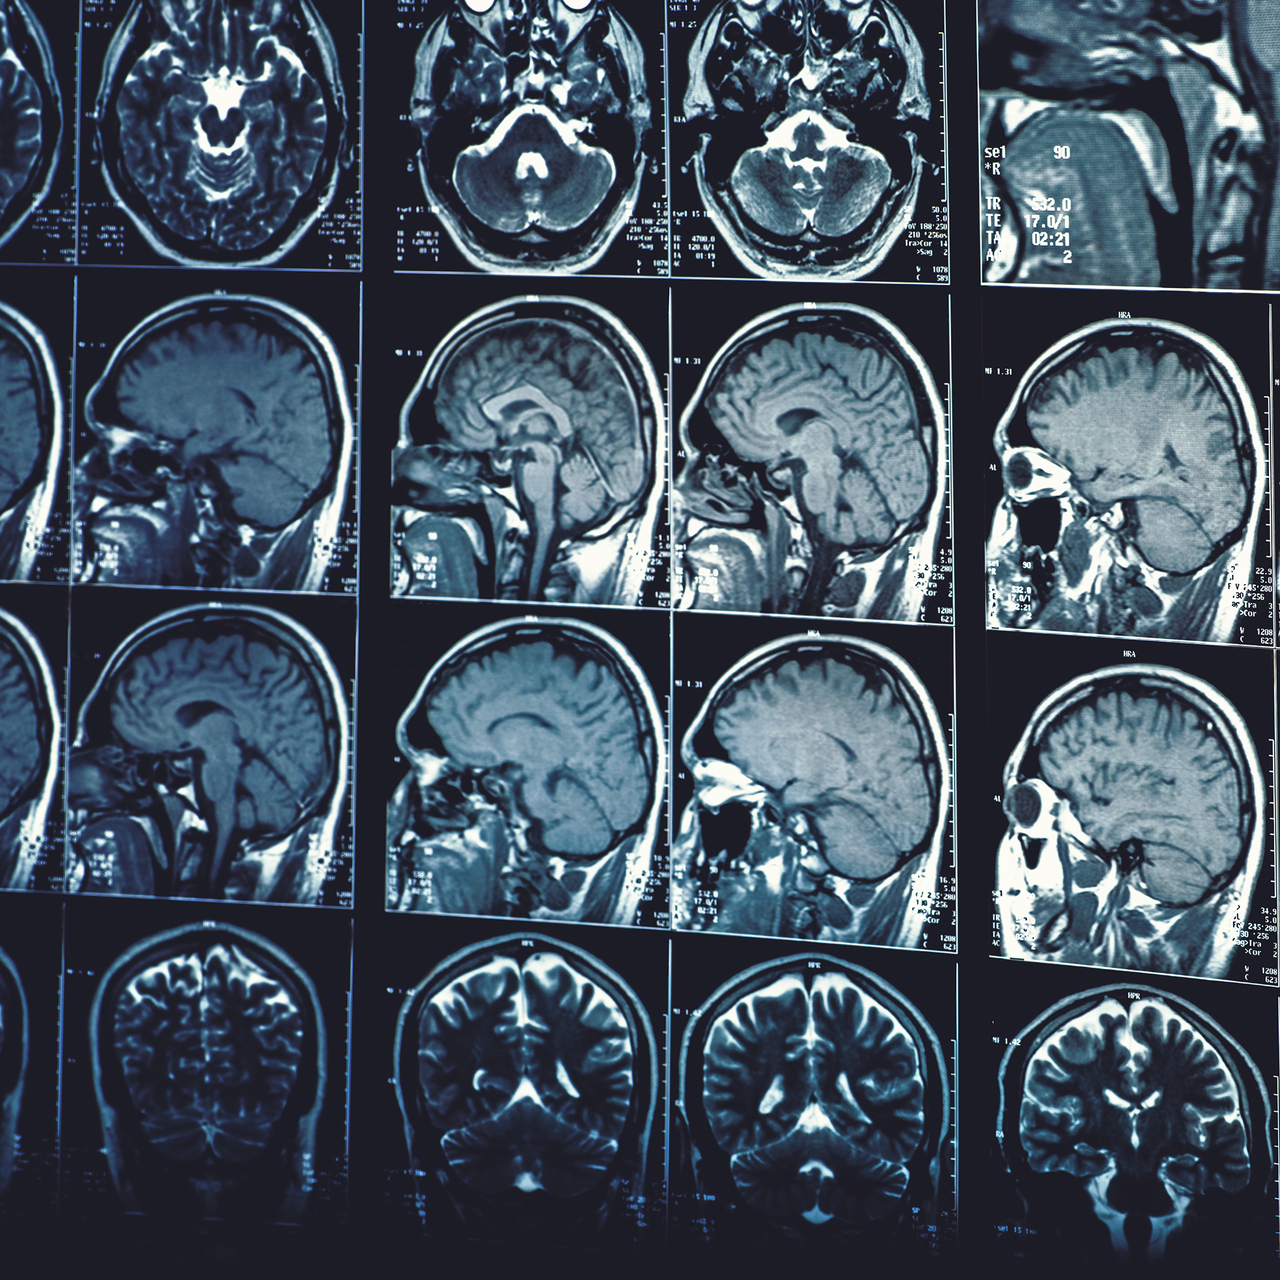

Mucize Organ Beyin Sempozyumu: İnme ve Beyin Hasarı Farkındalığı İstanbul’da bu yıl dördüncüsü düzenlenen ‘Mucize Organ Beyin Sempozyumu’, alanında uzman profesyonelleri ve inme geçirmiş ve hayata tutunmuş hastaları bir araya getirdi. İnme ve beyin hasarı yaşayan hastalar yeni bir hayata başladı ve bu yolculuk sürecini sempozyumda anlattı. İnmede acil müdahalenin...